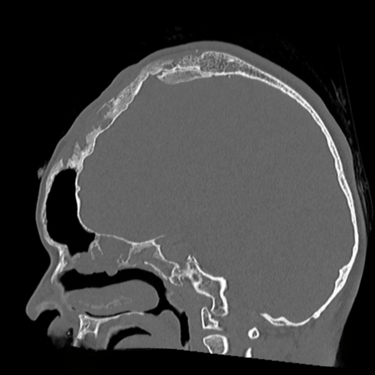

Osteomielitis Frontal | Diagnóstico por Tomografía

La osteomielitis frontal es una infección del hueso craneal que generalmente se origina como complicación de una sinusitis frontal no tratada o mal resuelta. Clínicamente puede manifestarse con dolor localizado, fiebre, edema frontal y signos inflamatorios en la región afectada. El método diagnóstico de elección es la tomografía computarizada (TC), que permite identificar destrucción ósea, engrosamiento cortical e incluso colecciones asociadas. Este estudio es esencial para diferenciarla de otras lesiones y planificar un tratamiento adecuado, que puede incluir antibióticos de amplio espectro y cirugía para drenar y desbridar el tejido infectado, evitando complicaciones intracraneales graves.